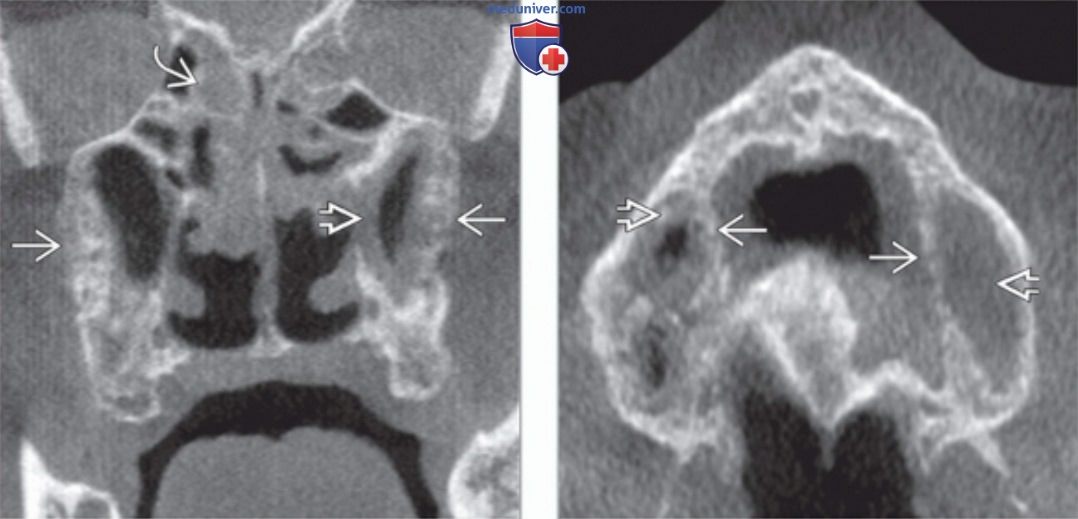

КТ-снимки хронического этмоидита: подробная визуализация